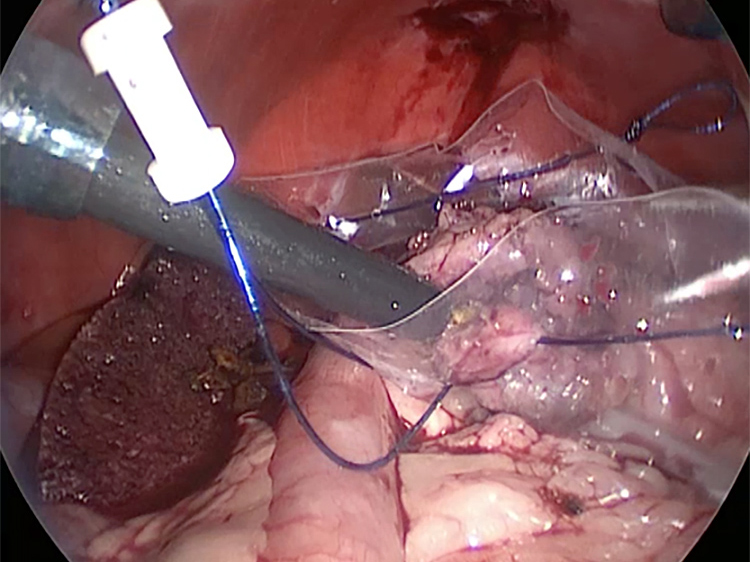

体の外に出すためお腹の中で袋に入れていきます。

このときに胆嚢と一緒にクリップやガーゼも回収します。そしてお腹の中をきれいにしていきます。

胆嚢を少しずつ丁寧に肝臓から剥がしています。

回収袋にいれて体外に摘出していきます。